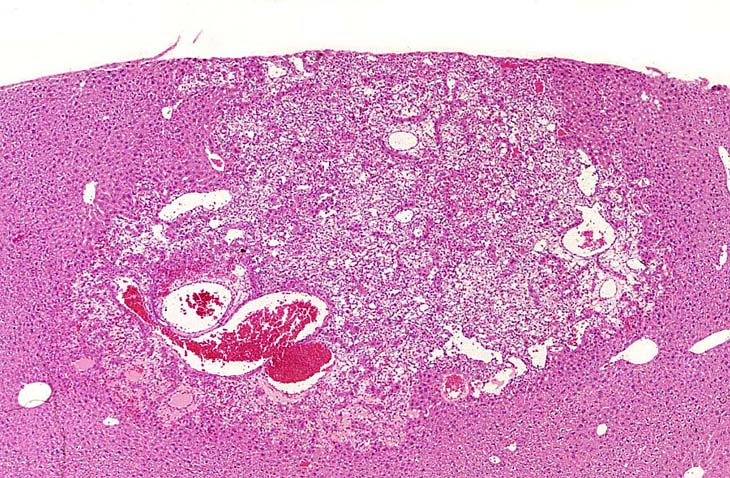

This Ito cell tumor is comprised of a mixture of stellate cells and mature adipocytes.